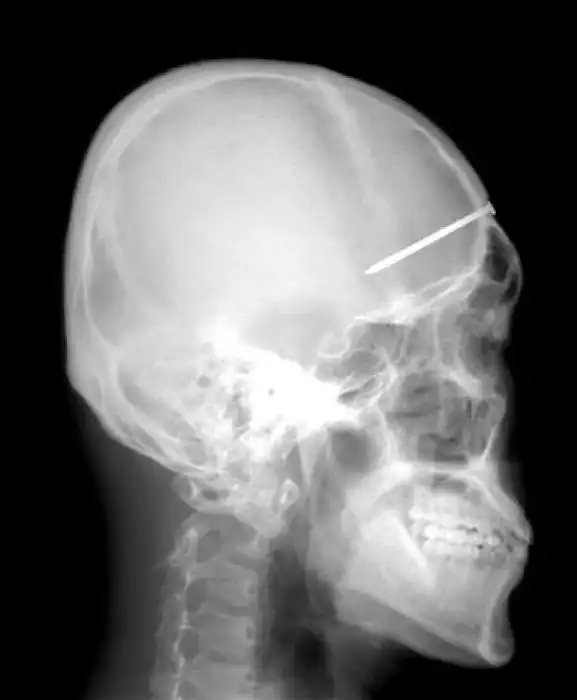

Необычные предметы в теле людей на рентгеновских снимках

На рентгеновских снимках людей порой можно обнаружить самые необычные предметы, которые находятся в их теле.